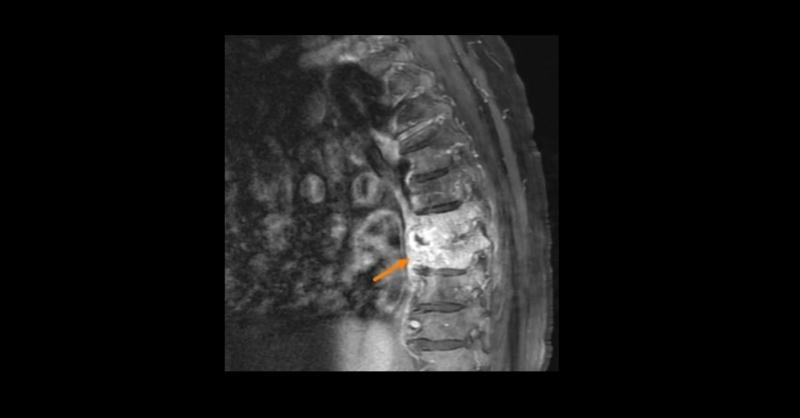

Proteus mirabilis is the second most common pathogen that causes urinary tract infections after Escherichia coli. In rare cases, it is associated with vertebral osteomyelitis. Vertebral osteomyelitis often presents with varied symptoms and is therefore a diagnostic challenge for clinicians. Treatment for vertebral osteomyelitis is usually conservat